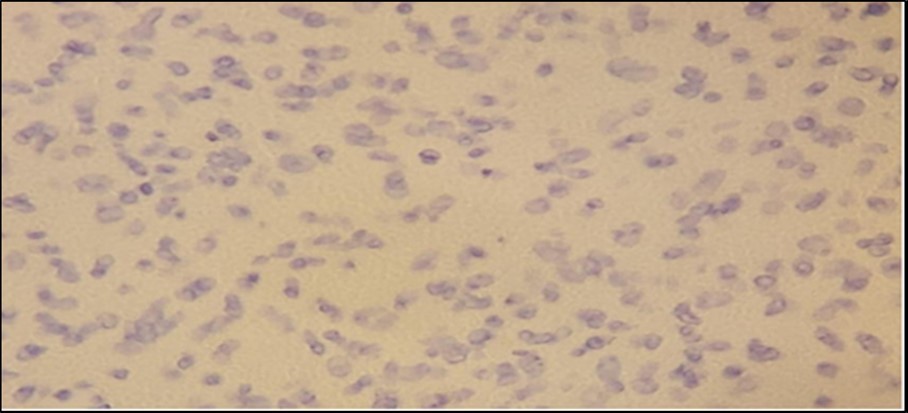

We have a case whose diagnosis needs to be confirmed. The previous biopsy showed histopathology consistent with a neurofibroma, with monomorphic, spindle-shaped, distinct cells, well-spaced, with scant mitosis. Neurofibromas are an autosomal dominant hereditary disease with a varied phenotype that affects the skin and nervous system. Affectation is one out of every 3,500 live births throughout the world. A spontaneous mutation on chromosome 17 is thought to be responsible for around half of the cases7. Figure 3. Comparison between biopsies taken five months apart. The histopathology in the biopsy done in February shows well-spaced uniform cells (black arrows). The biopsy done in July shows cellular congestion with atypical, pleomorphic cells with increased mitotic activity (blue arrows). In the most recent procedure, routine histopathology showed a different picture with higher mitotic figures and cellular congestion. The increased mitotic activity causes cellular production at a greater rate that the resulting cells show atypia and ill-defined borders. Hemorrhage and necrosis are also evident, hinting the tumor growth exceeds its vascular supply. The rapid clinical growth supported the high proliferative nature of the tumor. A diagnosis of Spindle cell sarcoma was made, with low to intermediate grade; however, a final diagnosis cannot be made based on morphology alone. To determine the type of malignancy, a panel of immunohistochemical stains was ordered. Table 1. Immunohistochemical Stain Marker S-100 Tumors of Mesenchymal origin (Sarcomas) SMA Myoepithelial cells Desmin Sarcoma vs Neurofibroma CD34 Epithelioid Sarcoma vs Dermatofibroma CK Tumors of Epithelial origin (Carcinomas) EMA Adenocarcinoma Three screening stains were ordered to identify the origin of the malignancy. S- 100 is a screening stain that becomes positive when exposed to mesenchymal cells. CK screens for malignancies of epithelial origin, while CD34 screens for hematopoietic involvement. Smooth Muscle Actin is a stain used to determine the presence of myoepithelial cells. This was chosen to consider the possibility of pulmonary metastasis. Desmin is a stain chosen due to its ability to differentiate rhabdomyosarcomas from other mesenchymal malignancies. Finally, EMA is a marker used to confirm carcinomatous lesions8 . Since the gross appearance of the tumor closely resembled muscular tissue, the S-100 stain was done first. The stain clearly showed a positive reaction. There was a note of mitotic activity in up to 7/10 high power fields with associated necrosis. This clinched the diagnosis as a mesenchymal tumor, allowing us to rule out three stains – CD34, CK, and EMA, along with their respective differentials of hematopoietic and epithelial tumors9. The initial positive reaction to S-100 allowed a narrowing of differentials to mesenchymal cell origin tumors. We could consider neurofibromas, schwannomas, malignant peripheral nerve sheath tumors, as well as metastatic myoepithelial cells. To help us differentiate, we take a closer look at SMA next. The sample did not stain to SMA, producing a negative result. This effectively ruled out myoepithelial tumors such as metastatic pleuropulmonary tumors, narrowing our differentials to neuronal tumors and smooth muscle rhabdomyosarcomas10. It was decided that determining desmin content would allow us to further narrow the differentials by differentiating between a rhabdomyosarcoma that would stain positively for desmin, and neuronal tumors such as a neurofibroma will be negative staining11,12 The specimen is composed of pleomorphic spindle cells forming sheets with a marbling pattern. Mitotic activity is present in up to 7/10 high power fields with associated crowding and necrosis. This portion of the lesion shows immunoreactivity for S100, while the remainder of the lesion has focal reactivity. Negative stains include SMA and Desmin. Since a neurofibroma can undergo malignant transformation, these last two lesions are what remain among our differentials. While morphologic histologic findings are more consistent with malignant growth, a closer look at the staining characteristics of S-100 can differentiate between the two lesions. In neurofibrosarcomas or malignant peripheral nerve sheath tumors, S100 staining is patchy and focal, with less than 50% of the specimen showing reactivity to staining. In neurofibromas, the S100 reaction is strong and diffuse, staining nearly the entire specimen13. The morphologic changes, immunohistochemical staining, and character of staining of S100 allows us to clinch the diagnosis of a Malignant Peripheral Nerve Sheath Tumor arising from a recurrent neurofibroma. Figure 4. Immunohistochemistry Staining results. S-100 shows selective staining of the cells of interest (black arrows). SMA and desmin showed negative staining of cells. In two population-based investigations, the lifetime probability of developing MPNST in NF1 patients was estimated to be 8-16 percent. Malignant transformation can begin as early as childhood, although it is most common in life's third to fourth decades. The probability of sarcoma-specific mortality is greatest in high-grade MPNST. Overall survival after five years ranges from 20% to 50%, with unresectable or metastatic cancer having a particularly poor prognosis14. Figure 5, Figure 6

Figure 3.Comparison between biopsies taken five months apart. The histopathology in the biopsy done in February shows well-spaced uniform cells (black arrows). The biopsy done in July shows cellular congestion with atypical, pleomorphic cells with increased mitotic activity (blue arrows).